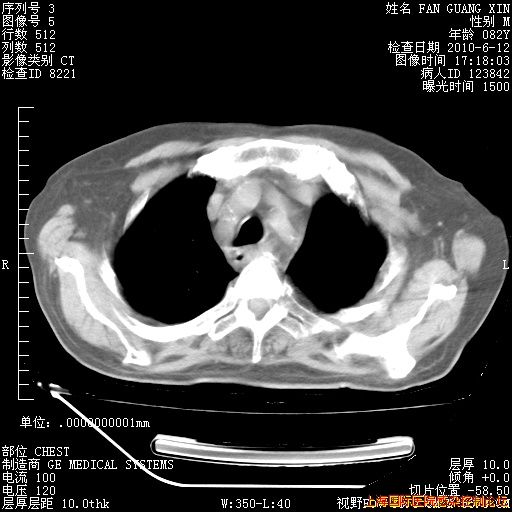

补发6月12日肺部CT肺窗

6月12日肺窗

6月12日纵膈窗